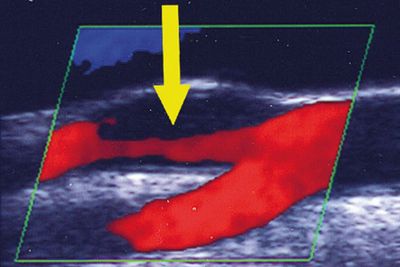

Farbkodierte extra- und transkranielle Duplexsonografie

Diese Methode bildet die Blutgefäße und den Blutfluss im Längs- oder Querschnitt ab. So werden Engstellen, Gefäßthrombosen oder Kalkablagerungen sichtbar.